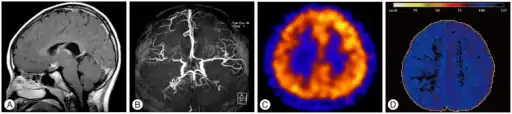

| T1-weighted MR image of moyamoya disease. Flow void in the basal ganglia is indicated by the arrow. | |

Magnetic resonance angiography (MRA) is also useful in diagnosing the disease with good correlation with Suzuki's grading system.[14]

Often nuclear medicine studies such as SPECT (single photon emission computerized tomography) are used to demonstrate the decreased blood and oxygen supply to areas of the brain involved with moyamoya disease. Conventional angiography provides the conclusive diagnosis of moyamoya disease in most cases and should be performed before any surgical considerations.